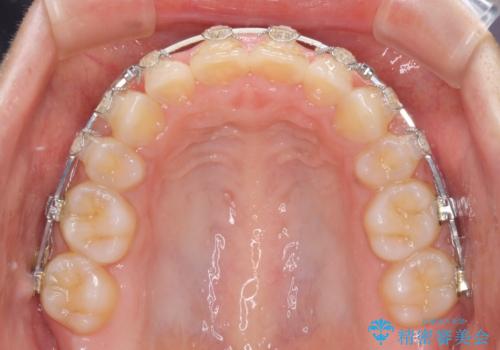

- 矯正装置

- 審美装置

- 4年5ヶ月

- 10-30回

上下左右の小臼歯4本を抜歯し、ワイヤー装置にて口元を引っ込めるよう矯正治療を行うこととしました。